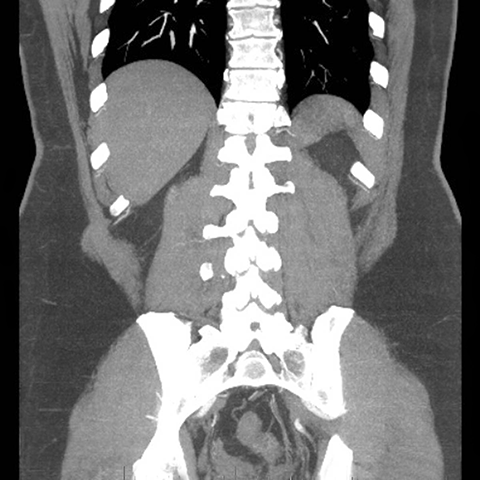

Abdominal Wall Muscles Normal Anatomy, Coronal CT [7 of 9]